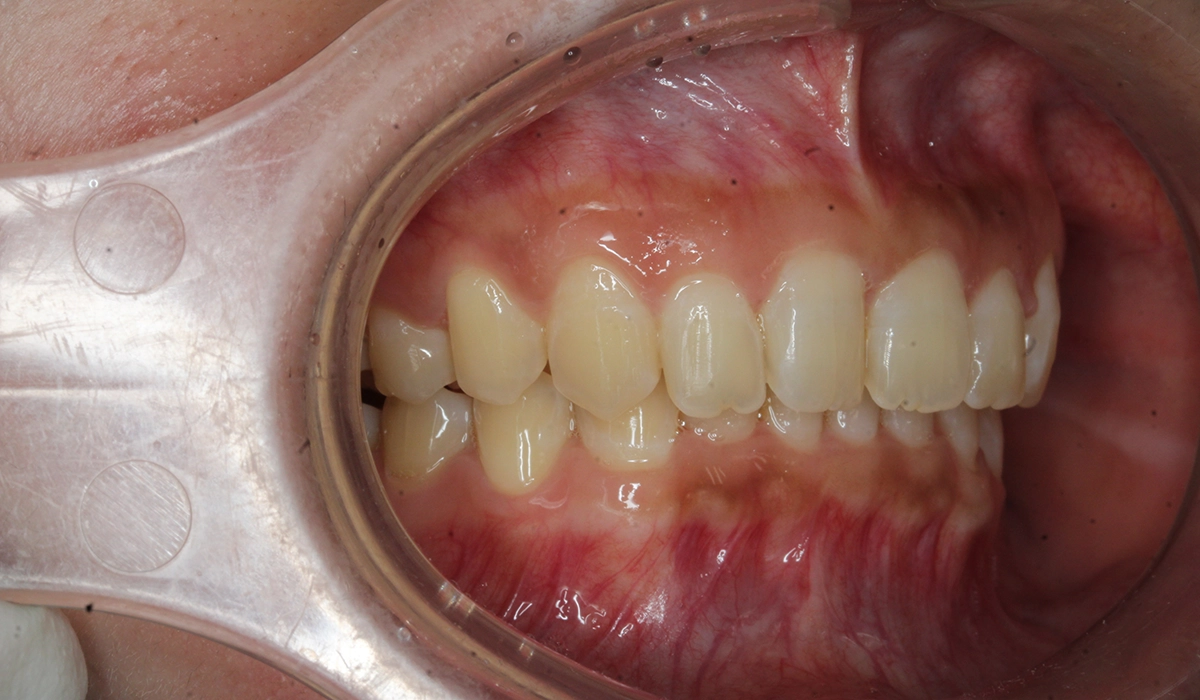

術前:左側

術後:左側